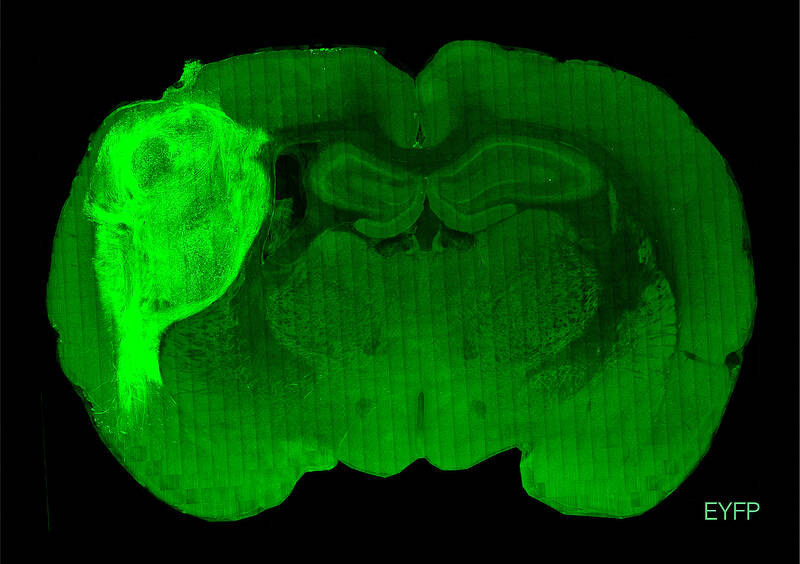

To overcome those limitations, researchers implanted the groupings of human brain cells, called organoids, into the brains of young rats.

“By transplanting them at these early stages, we found that these organoids can grow relatively large, they become vascularized (receive nutrients) by the rat, and they can cover about a third of a rat’s (brain) hemisphere,” Pasca said.